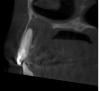

kenig Опубликовано 18 октября, 2012 Поделиться Опубликовано 18 октября, 2012 (изменено) Июль 12г.Жалобы:постоянный привкус гноя во рту, по утрам под губой белый сгусток, каждые три дня распухает небо, при нажатии на небо выделяется гной в области 12 зуба.Объективно:11 зуб покрыт исскуственной коронкой, 12 временная реставрация (находится на этапе лечения), 13 зуб интактный. В области 12 зуба с вестибулярной стороны свищ.R-гр.: киста вобласти 11,12,13 зубов.Анамнез: 12 зуб лечат год в другом лечебном учреждении, безуспешно, ничего не меняется.Рекомендовано:КТ верхней челюстиЭндо-лечение 11,12,13 зубов. Проведено лечение 11 зуба-коффердам, хлорка, лимонка, каласепт на две недели,пломбирование-вертикалка. Результат-пациент счастлив-привкус гноя пропал, под губой по утрам ничего нет, распухает раз внеделю. Свищ на месте. Проведено лечение 13 зуба-коффердам, хлорка, лимонка,каласепт на две недели, пломбирование-вертикалка. Все это время 12 зуб моем, моем,но из него все время льется, хотя через 10-20 минут мытья его возможно высушить.Результат-еще лучше, распухает раз в две недели. Свищ на месте..Сентябрь-наконец-то принесли КТ-ужас. В процессе небный корень 14 зуба, хотя реагирует на холод как витальный зуб. Небно нет кости от 11 до 14 зуба, в области 11 зуба сообщение с полостью носа. Вопросы:Эндо 14 зубу проводить? Реагирует на холод, как живой.12 зуб пломбировать? Просушить его возможно через минут 10-20 мытья. Временные промежутки между обострениями увеличиваются, но меня результат не радует.Как бы поступили Вы в такой клинической ситуации? -диагностический 12 зуба-контрольный 11 зуба-контрольный 13 зуба-КТ 11 зуба-КТ 12 зуба-КТ 13 зуба-КТ 14 зуба был подобный случай, причинный был 22, эндо с апексификацией 22, гидроокись не приносила ожидаемых результатов, раз 5 получал несколько 2-кубовых шприца желтой опалесцирующей жидкости, потом высушил, запаковал МТА, хоирург сделал декомпрессию по парч, полтора года мыли хлоргексидином раз в 2 недели, вот что получилось, без всякой хирургии Изменено 18 октября, 2012 пользователем kenig 1 Ссылка на комментарий